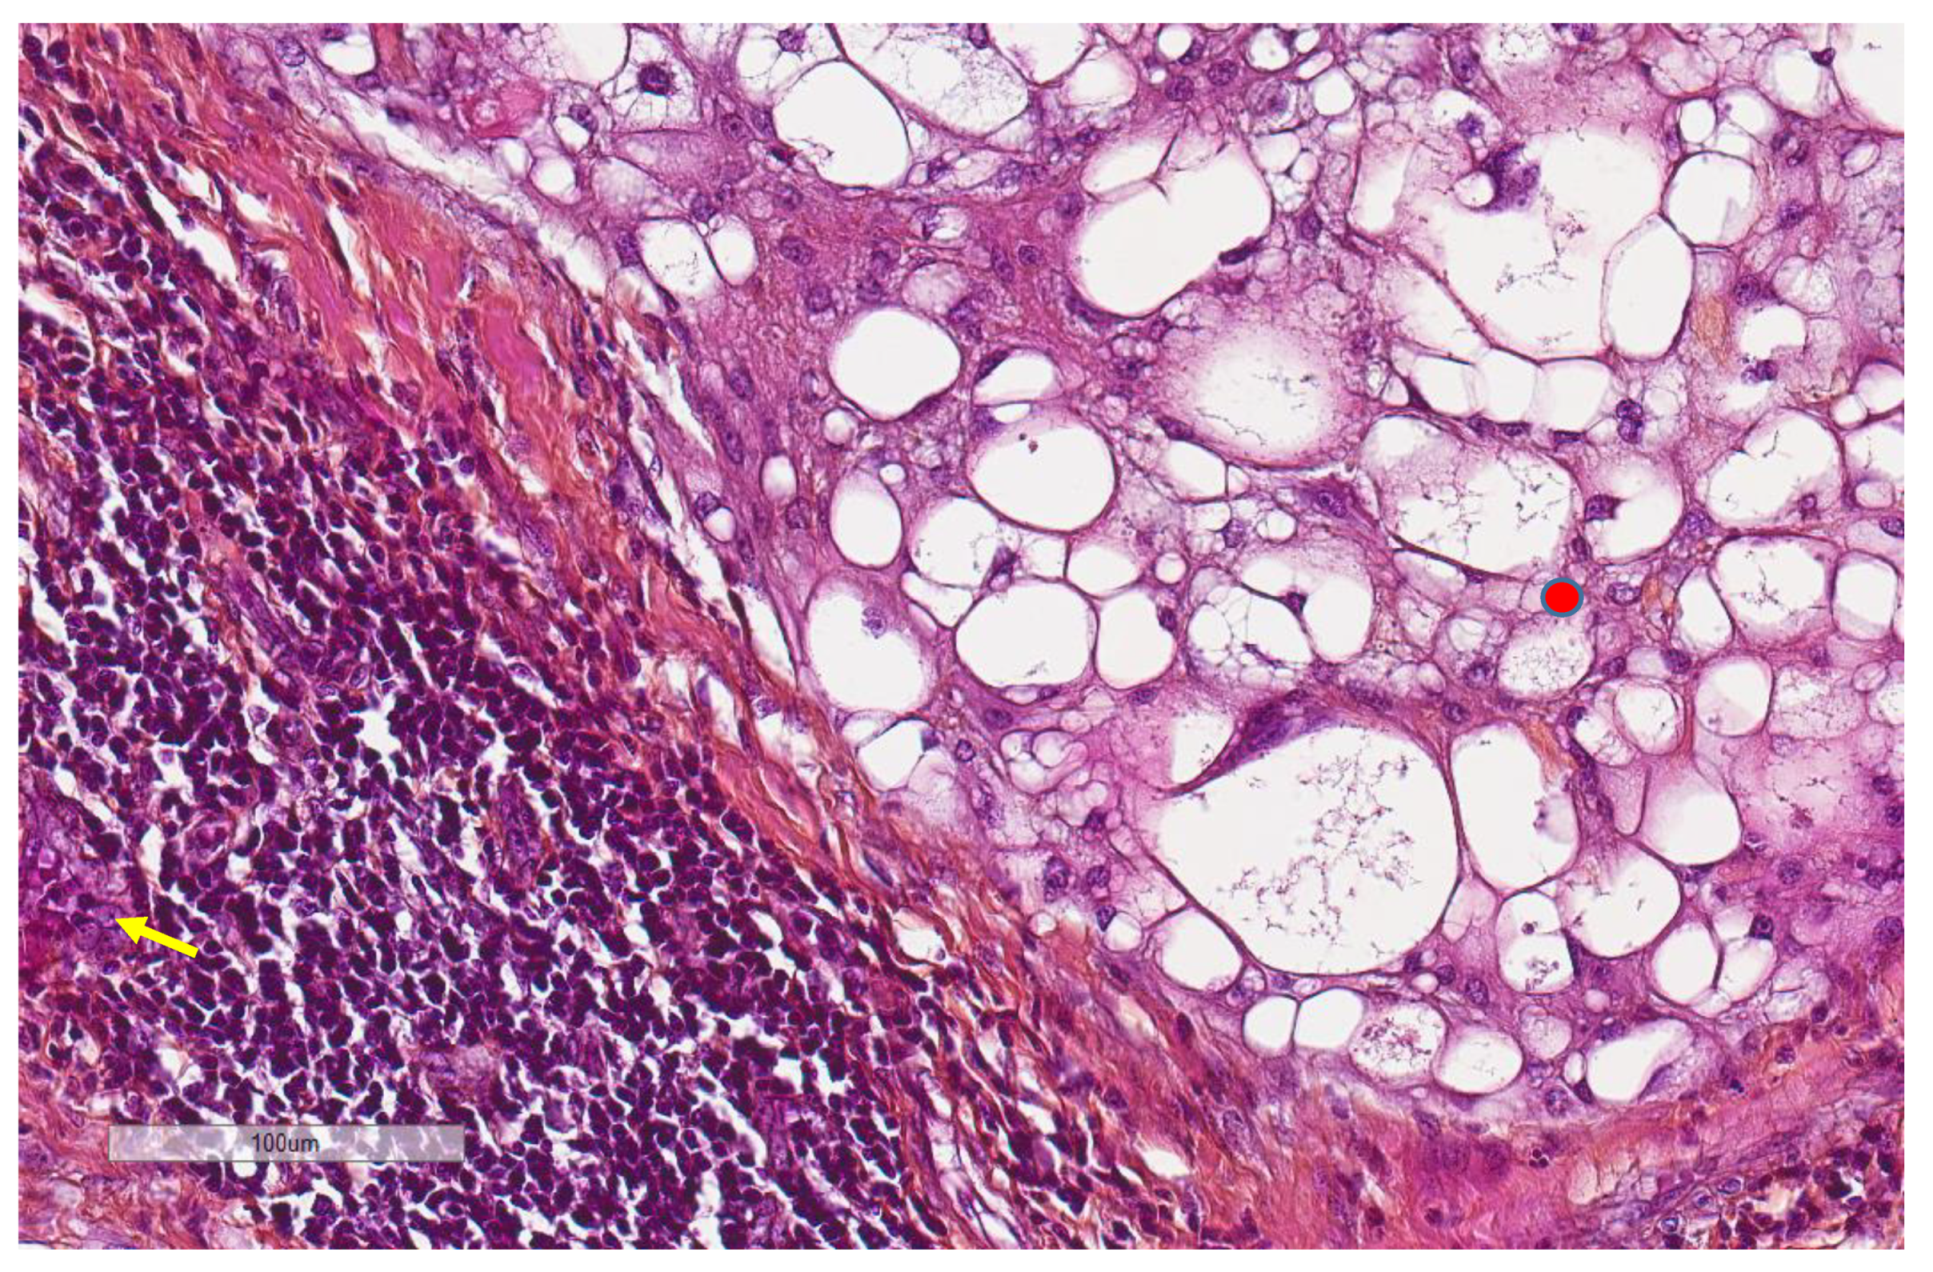

| MECA-79 vessels (n = 59) | |

| High | 5, 8.5% |

| Low | 54, 91.5% |